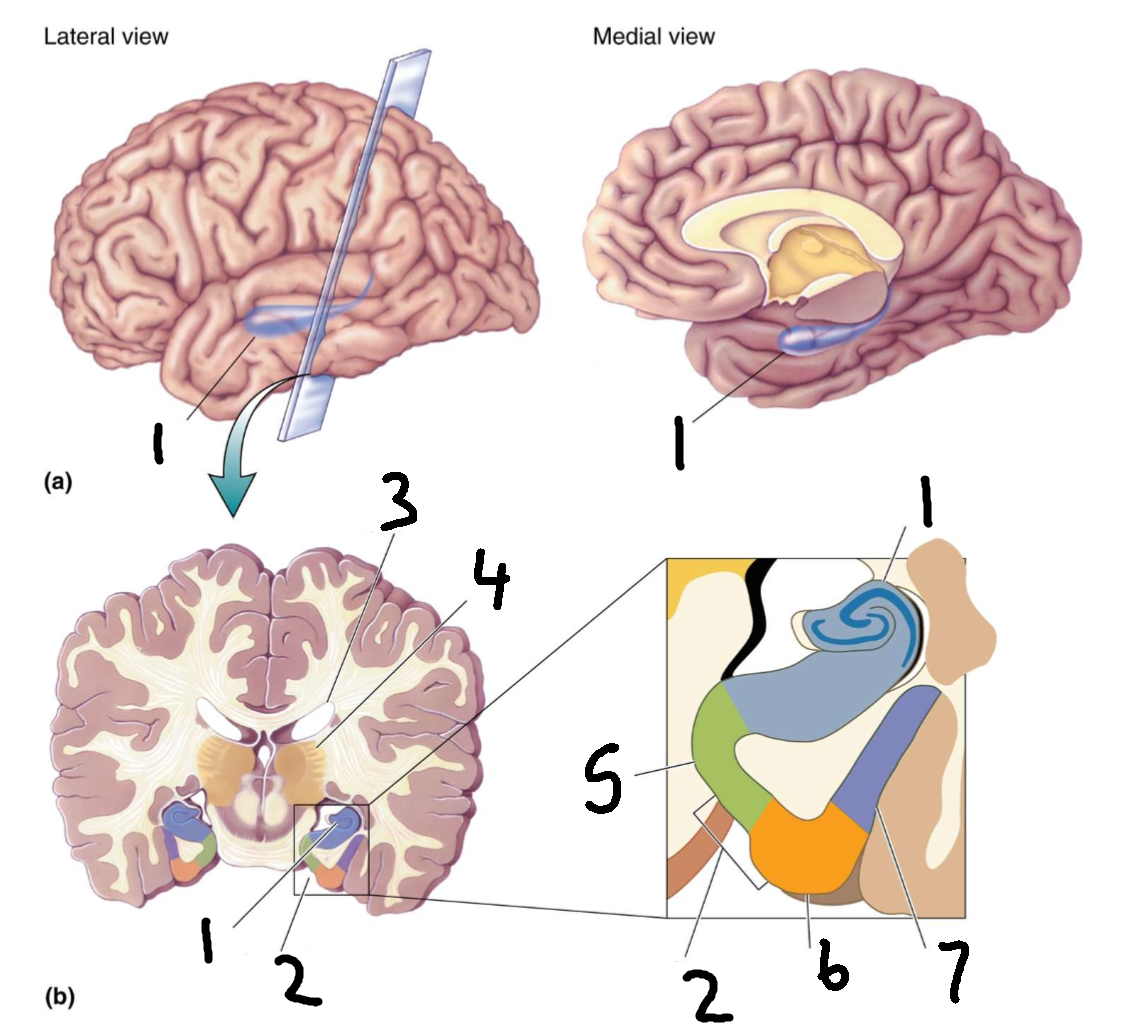

What is 1?

cingulate gyrus

What is 2?

corpus callosum

What is 3?

fornix

What is 4?

cut edge of midbrain

What is 5?

parahippocampal gyrus

What structure is this?

hippocampus

What is 1?

hippocampus

What is 2?

rhinal sulcus

What is 3?

lateral ventricle

What is 4?

thalamus

What is 5?

entorhinal cortex

What is 6?

perirhinal cortex

What is 7?

parahippocampal cortex